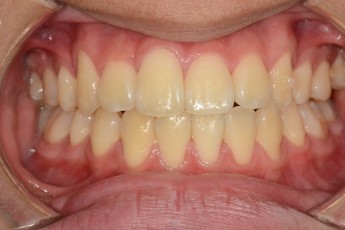

Before

After